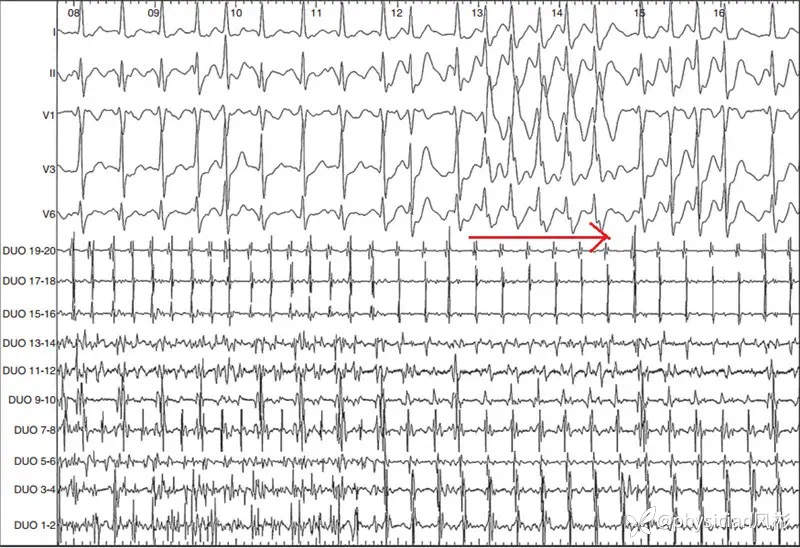

Case 2:患者为77岁男性,既往高血压病史,口服卡托普利降压治疗,否认结构性心脏病,心功能正常,入院前曾因阵发性房颤行电复律治疗。本次入院行射频消融术,术中患者窦性心律,放置20极Halo电极时激发患者房颤,持续10分钟,当决定终止房颤静脉给予维纳卡兰3 mg/kg后,患者由房颤转为宽QRS波心动过速(图4)。

图4. 患者术中激发房颤,静脉输注维纳卡兰后出现宽QRS波心动过速(红色箭头所示)

如上图所示,体表心电图下为同步记录的心腔内电图,DUO为右心房放置的Halo电极,可见,心房颤动时,Halo电极记录到紊乱的心房电活动,宽qrs波心动过速时心房电活动趋于有序,心房电活动的周期接近相等。

心电图检查示宽QRS波心动过速,右束支传导阻滞。后经电生理检查为房扑1:1下传,心房周期320 ms,与心室周期传导一致,无房室分离,证实为房扑1:1下传。

图5. A:心电图检查示右束支阻滞型宽QRS波心动过速;B:电生理证实宽QRS波心动过速为房扑1:1下传(DUO为Halo电极,激动顺序表明是逆钟向激动的典型房扑)。